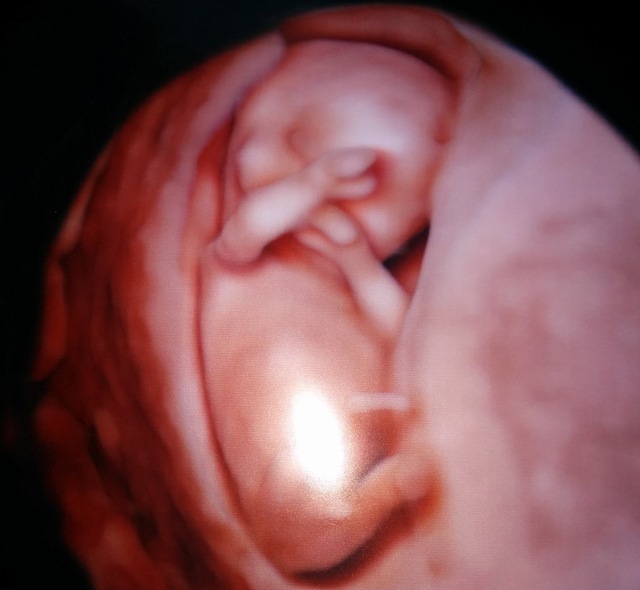

12週2日(12w2d・男の子)|むむちゃん さん(38歳)

エコー写真撮影時のエピソード:

はじめて3Dエコーで見たときの画像です。左手を挙げ「ハーイ!」と挨拶されました。夫婦で病院に行き一緒に見ることができたのもうれしかったです。

先生にもとても珍しいポーズと言われました。産まれてからもやたらと手足が激しく動く赤ちゃんでお腹にいた時からだなーといつも思ってます。